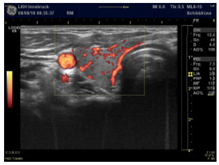

| Slight increase with a point-like pattern—suggests magnesium deficiency | |

| Moderate increase with a wire-like pattern—suggests CoQ10 deficiency | |

| Very intense hyper-perfusion—suggests a severe combined deficiency condition | |

| Power Doppler Images | ![]() | ![]() | ![]() |

| Condition | Magnesium def. pattern | CoQ10 def. pattern | Chronic fibrosis |